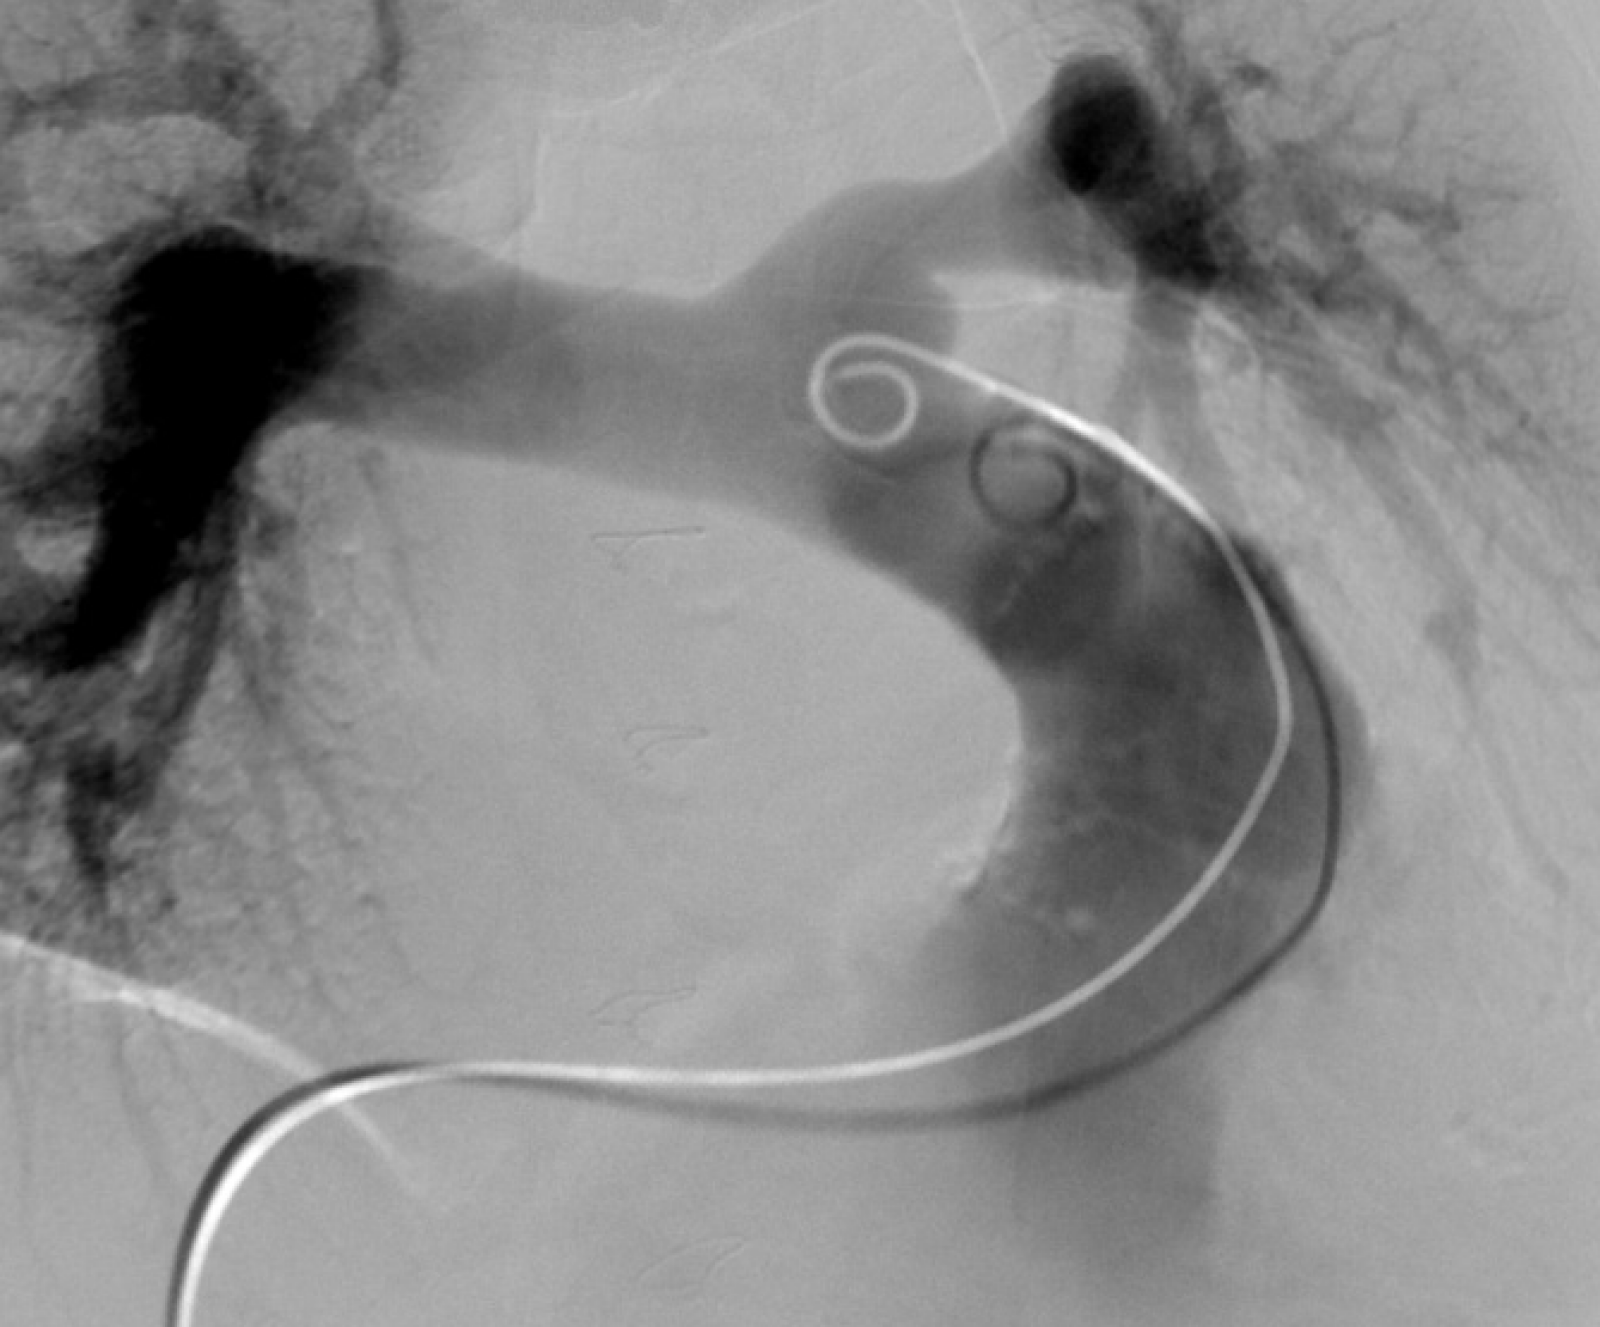

Centrum komplexní péče o vrozené srdeční vady v dospělosti vzniklo  v roce 2015  díky spolupráci  Centra kardiovaskulární a transplantační chirurgie s Interní kardiologickou klinikou Fakultní nemocnice  Brno a nabízí zcela komplexní péči o dospělé nemocné s vrozenou srdeční vadou. Portfolia jednotlivých pracovišť se navzájem doplňují.  Centrum poskytuje ambulantní sledování pacientů se všemi typy vrozených srdečních vad, neinvazivní a invazivní diagnostiku včetně transesofageální echokardiografie s využitím 3D zobrazení.  Centrum kardiovaskulární a transplantační chirurgie Brno provádí operace, reoperace a  intervenční výkony u vrozených srdečních vad a současně se věnuje chirurgické léčbě pokročilého srdečního selhání vč. implantace mechanických srdečních podpor a transplantace srdce ( Tým lékařů , seznam prováděných operačních a intervenčních výkonů).  V rámci Interní kardiologické kliniky FN Brno poskytuje invazivní  řešení arytmií ( radiofrekvenční ablace, kardiostimulace vč. resynchronizační léčby), některé intervence (uzávěry defektů septa síní) , organizaci nekardiálních operací a péči o gravidní včetně porodu probíhají v rámci Interní kardiologické kliniky FN Brno.   Návaznost na kardiologii dětského věku je zajištěna spoluprací s Fakultní dětskou nemocnicí v Brně.  Ambulantní péče probíhá na obou klinikách paralelně.